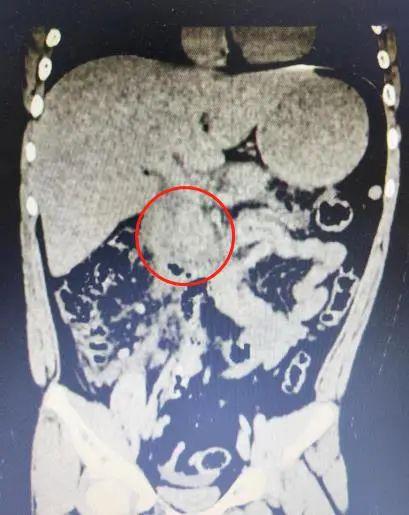

听到这里,医生高度怀疑胰腺炎的可能,立即为球球完善抽血和CT检查,结果提示胰腺炎的指标——血淀粉酶高达553单位/升,大大超出了正常范围(正常值为35-135单位/升),CT显示胰腺水肿渗出。球球被诊断为急性胰腺炎。